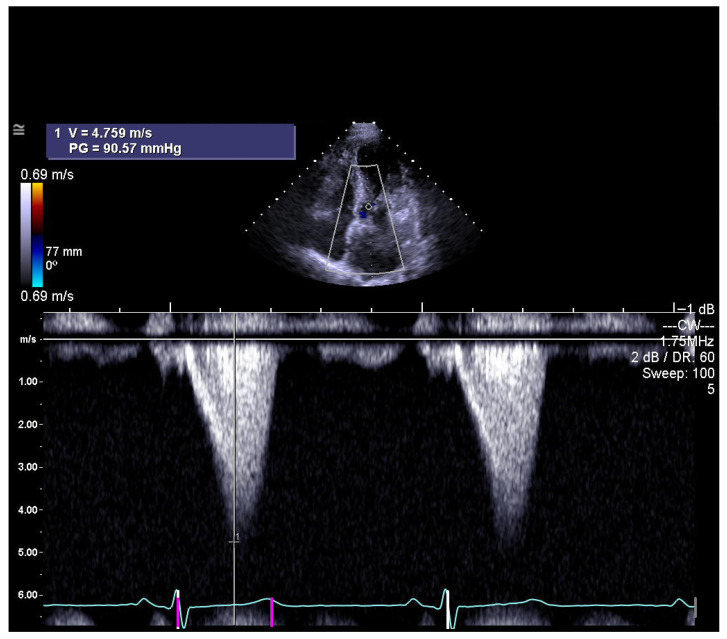

背景/目的:本研究旨在探讨肥厚性心肌病(HCM)患者右心室(RV)结构和功能之间的关系,并建立酒精间隔消融术(ASA)疗效的标志物。我们假设右心室特征可以作为ASA后早期左心室流出道梯度(LVOTG)的预测因子。方法:对50例接受ASA治疗的HCM患者进行回顾性分析。在术后3个月、1年、3年和5年评估超声心动图RV参数与ASA成功标准指标的相关性。结果:ASA后3个月和1年的左室壁厚(RVWT)与最大LVOTG (p < 0.001)、NYHA功能分级和左室舒张末期尺寸(LVD)均有显著相关性(p < 0.01)。在第3年和第5年,这些相关性不再具有统计学意义(p = ns)。其他参数未观察到关联。结论:超声心动图评估RVWT可作为ASA后3个月LVOTG发展的早期预测指标。因此,RVWT可以提供长期治疗效果的估计。需要进一步的研究来证实这些发现。

Background/Objectives: This study aimed to investigate the association between right ventricular (RV) structure and function and established markers of alcohol septal ablation (ASA) efficacy in patients with hypertrophic cardiomyopathy (HCM). We hypothesized that RV characteristics may serve as predictors of left ventricular outflow tract gradient (LVOTG) in the early period following ASA. Methods: A retrospective analysis was performed in 50 HCM patients who underwent ASA. Correlations between echocardiographic RV parameters and standard indicators of ASA success were assessed at 3 months, 1 year, 3 years, and 5 years post-procedure. Results: Echocardiographic measurements of RV wall thickness (RVWT) at 3 months and 1 year after ASA showed significant correlations with maximum LVOTG (p < 0.001), NYHA functional class, and left ventricular end-diastolic dimension (LVD) (both p < 0.01). At 3 and 5 years, these correlations were no longer statistically significant (p = ns). No associations were observed for other parameters. Conclusions: Echocardiographic assessment of RVWT may serve as an early predictor of subsequent LVOTG development as soon as 3 months after ASA. RVWT could therefore provide an estimate of long-term treatment effects. Further studies are needed to confirm these findings.